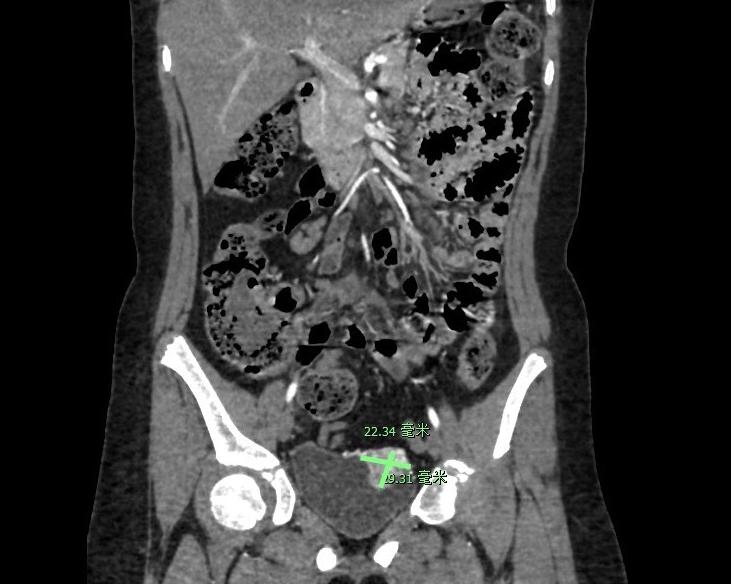

手術前,CT檢查顯示,盈盈的膀胱壁上發現一個2—3cm大小的腫物,高度懷疑為嗜鉻細胞瘤

6月2日,盈盈隨家人到深圳市兒童醫院就診。經過醫生仔細檢查,盈盈的血壓偏高,最高時達到157/102 mmHg,比正常值高出不少。同時,還在她的膀胱壁上發現一個2—3cm大小的腫物。結合盈盈高血壓的發病規律以及臨床表現,醫生推測這個拇指大小的腫塊,是一種引起惡性血壓升高的罕見疾病——嗜鉻細胞瘤。